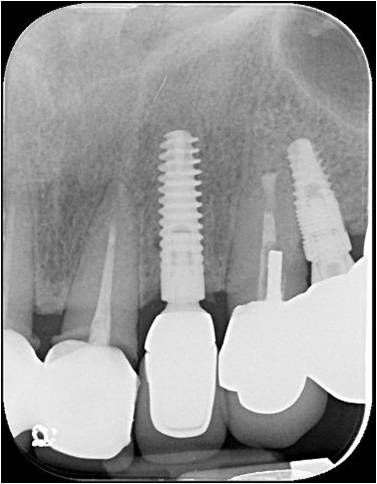

治療後X光